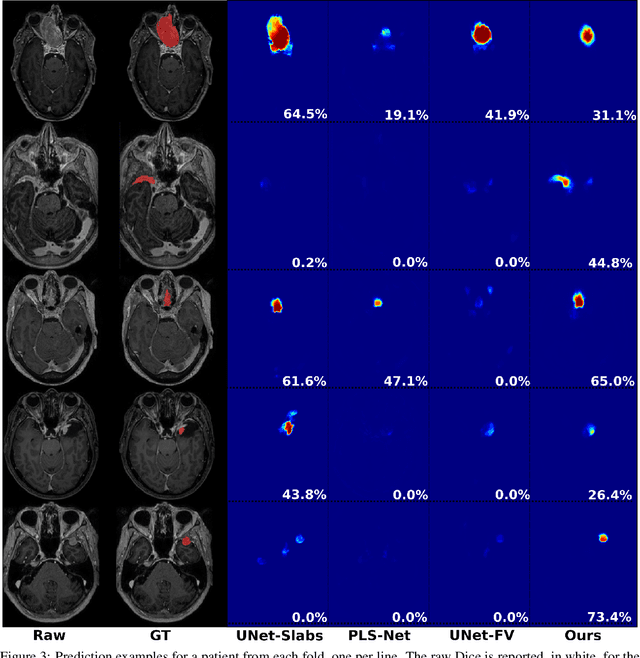

Abstract:Extent of resection after surgery is one of the main prognostic factors for patients diagnosed with glioblastoma. To achieve this, accurate segmentation and classification of residual tumor from post-operative MR images is essential. The current standard method for estimating it is subject to high inter- and intra-rater variability, and an automated method for segmentation of residual tumor in early post-operative MRI could lead to a more accurate estimation of extent of resection. In this study, two state-of-the-art neural network architectures for pre-operative segmentation were trained for the task. The models were extensively validated on a multicenter dataset with nearly 1000 patients, from 12 hospitals in Europe and the United States. The best performance achieved was a 61\% Dice score, and the best classification performance was about 80\% balanced accuracy, with a demonstrated ability to generalize across hospitals. In addition, the segmentation performance of the best models was on par with human expert raters. The predicted segmentations can be used to accurately classify the patients into those with residual tumor, and those with gross total resection.